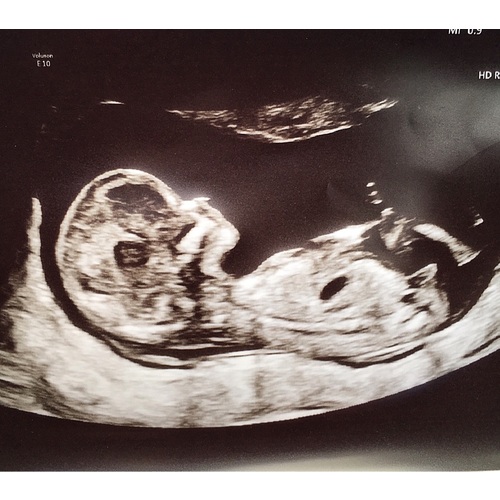

In bijlage zie je onze laatste echo van 12w1d. Wat denken jullie? En is dat nu het befaamde nubstaartje of eerder een stukje bot van iets anders 🤗